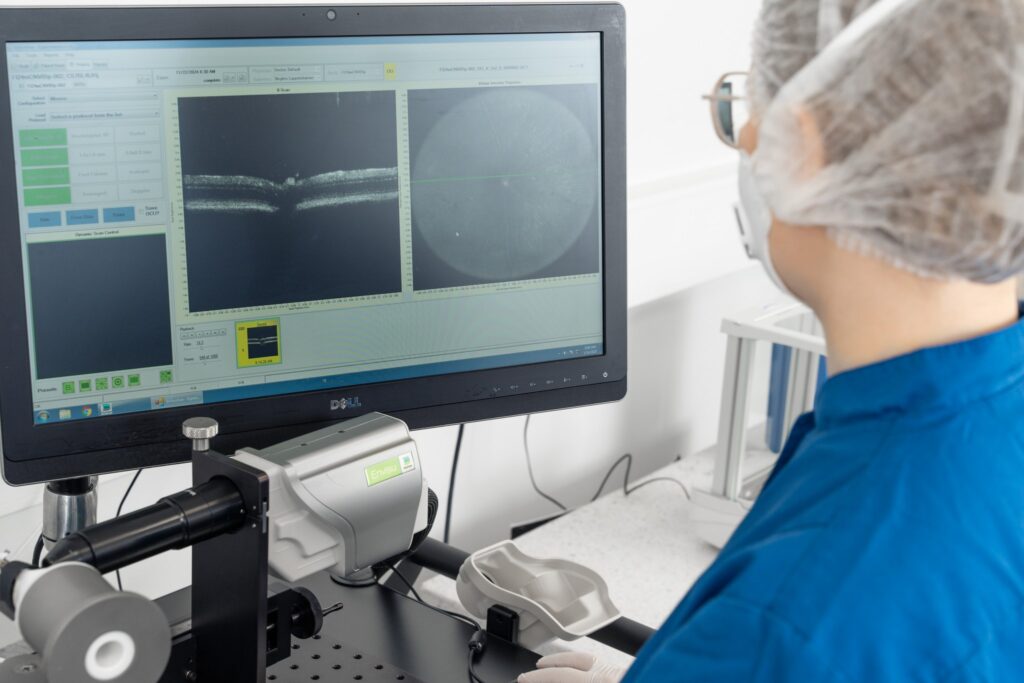

Experimentica employs state-of-the-art in vivo imaging for longitudinal monitoring of NAION pathology. SD-OCT enables cross-sectional visualization of the optic nerve head and retina to assess edema and retinal layer thinning (Ragauskas et al., 2018). Retinal ganglion cell (RGC) function is evaluated using pattern electroretinography (pERG), visual acuity and contrast sensitivity (OMR). RGC loss is confirmed by immunolabeling in retinal flatmounts, and optic nerve damage is assessed through histological sectioning and staining.

– Quantitative data from in vivo imaging and AI-driven segmentation analysis (SD-OCT)